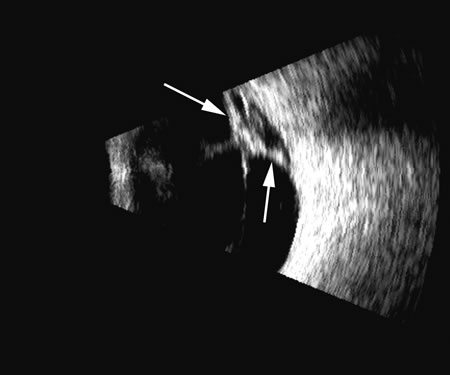

Fresh blood in the vitreous may be acoustically clear since the red cells may not have congealed sufficiently to form a good echo-producing surface.8 A retracted “hyaloid” or posterior limiting membrane (PLM) of the vitreous can be shown with most B-scan instruments, but paradoxically a retracted vitreous may not be seen as well with higher-resolution, more highly focused transducers because they display less area of the reflective surface. Blood collected on the surface of the PLM enhances this surface and may, in some cases, make the PLM resemble a detached retina, since its anatomic dimensions can be similar to the retina. Three differences may help distinguish the two structures. First, kinetic scanning reveals a lack of attachment at the optic nerve for a PLM. Second, the PLM is irregular in reflection and thickness (usually thicker than the retina) between the ora and the disc, and usually the surface cannot be traced forward to the ora on the B-scan display. Third, the amplitude of the echoes from the PLM is lower than from the retina, except when directly perpendicular to the beam, where they may be similar in amplitude. Many of these features of a PLM are demonstrated in Figure 7, whereas Figure 8 shows a typical detached retina.

Fig. 7. This B-scan ultrasonogram demonstrates retinitis proliferans with typical vitreous membrane attaching to the proliferative membrane (arrows) that can resemble a traction detachment. Scanning at right angles helps distinguish proliferative membranes from retinal traction membranes, as they have less reflectivity than retina.